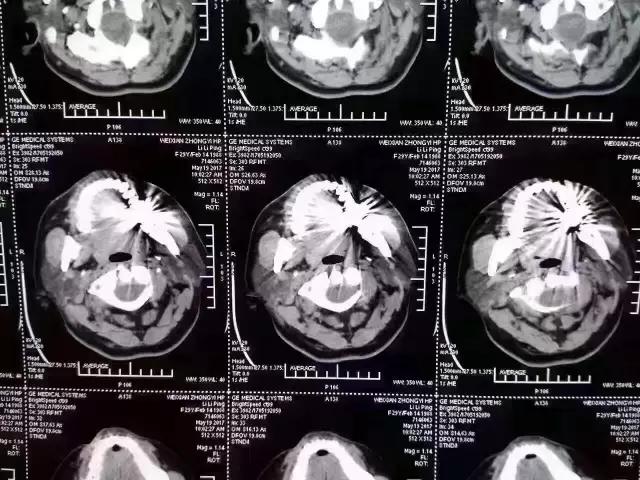

曾经,一张照片刷爆了牙医朋友圈

对这张照片,有牙医评论如下:

口内有金属烤瓷牙做核磁共振,CT,以烤瓷牙为中心呈现放射状影像,无法看清周围组织,影响临床诊断,建议条件允许的朋友还是选择二氧化锆全瓷冠修复,以免带来不必要的麻烦!